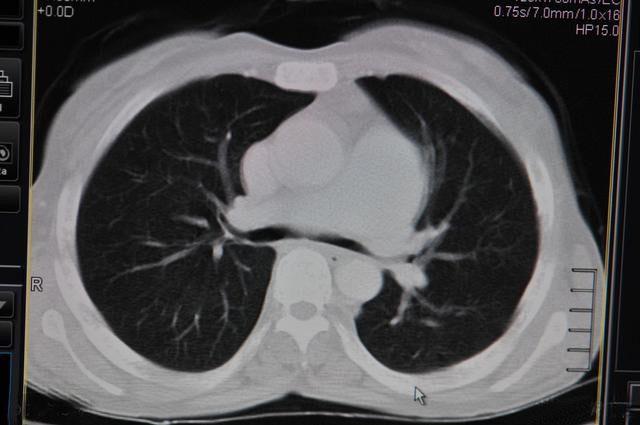

正常情况下,肺泡中只有空气,没有有形成分,在胸部CT上由于肺泡壁纤细,所以被其中充满的空气所“淹没”,就像渔网撒入水中而湮灭一样,所以在胸部CT上肺组织除了其中较粗的血管和支气管,大部分呈现出黑色无有形成分的样子,当一些肺泡被液体、细胞、纤维素等有形成分充满时,在CT上就可能表现出一些白色有别于正常黑色肺组织的表现,这些白色的有形成分称为“病灶”,肺部小结节是其中比较特殊的一种病灶,大部分为实密的细胞成分构成,这些成分通常呈同心圆样排列,周围以淋巴细胞为主,中间可能存在一些巨噬细胞残体,杂以纤维母细胞,称为肉芽肿,这种肉芽肿性病变可以说是肺部小结节的最主要形式,肉芽肿性病变都是良性的,另外,3cm以下的球性病灶称为结节,3cm以上的称为肿块。